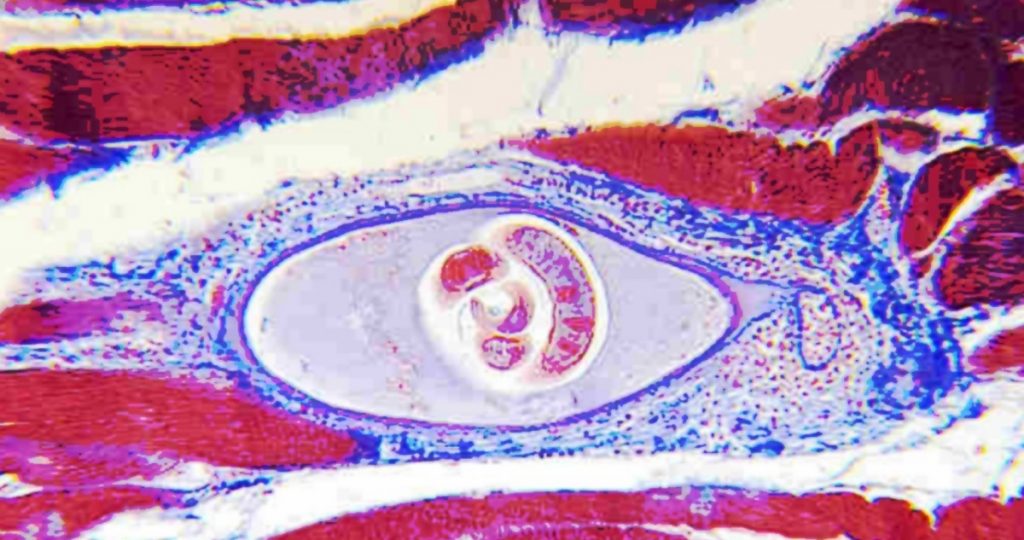

In queste ultime settimane si sta parlando in Italia molto della trichinellosi, una malattia causata…